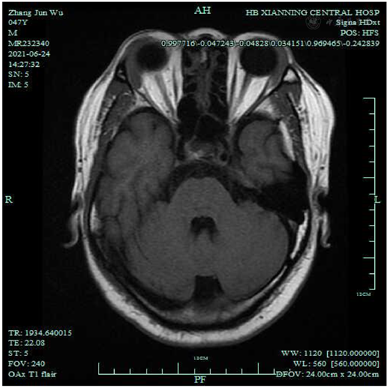

入院后完善相关检查:血液分析(五分类):嗜酸性粒细胞(#) 0.69×109/L↑;嗜酸性粒细胞(%) 13.00%↑;红细胞4.28×1012/L ↓;血红蛋白129.0 g/L ↓;红细胞压积37.6%↓;肝肾功能:尿酸477 umol/L ↑;白蛋白36.0 g/L ↓;球蛋白44.7 g/L ↑;白球比0.8 ↓。凝血功能五项、尿分析+尿沉渣定量、粪便常规+潜血+寄生虫未见异常。甲功五项、男性肿瘤标志物:未见异常,感染性疾病筛查(输血科):乙肝病毒表面抗体30.62 mIU/ml ↑;免疫球蛋白+补体定量测定:免疫球蛋白G 2040.2 mg/dl ↑,自身免疫抗体全套2(ANA核型、ANA定量、ENA谱):阴性。颌下腺MR平扫诊断内容:1.左侧腋窝淋巴结肿大;2.双侧颌下区、颈部小淋巴结显影。头颅MRI平扫诊断内容:颅脑MRI扫描未见明显异常。CT-平扫全腹诊断内容:胆囊切除术后改变。CT-平扫胸部及心脏诊断内容:右肺上叶少许炎症。免疫球蛋白G4 53.6 g/L↑,考虑IgG4相关性疾病,至华中科技大学同济医学院附属同济医院就诊,磁共振-眼眶平扫:双侧泪腺肿胀;冠状位TW1扫描所及双侧腮腺体积增大;双侧筛窦和额窦炎。再次重新阅读我院头颅MRI(图1)及颌下腺MRI (图2A、B)可发现患者泪腺、腮腺及颌下腺均肿大。于华中科技大学同济医学院附属同济医院口腔科行左侧颌下腺切除,病检结果:灰红不整涎腺组织4.6 cm×3 cm×2 cm,临床已部分切开,切面灰红分页状,未见明确实性肿块,病理诊断:(左颌下肿物)镜下见涎腺小叶被增生的纤维结缔组织分隔,小叶内外可见浆细胞为主的慢性炎性细胞浸润,淋巴滤泡增生,免疫组化结果提示IgG阳性细胞数热点区约100个/HPF,且IgG4/IgG大于40%,考虑IgG4相关性疾病可能性大。免疫组化:浆细胞IgG4热点区约150个/HPF,且IgG4/IgG大于40%,CD19(+),κ和λ(部分阳性,无限制性轻链表达),淋巴滤泡CD20(+,阳性对照+),CD21(FDC网+),ki-67(生发中心高,滤泡间区散在+);滤泡间区CD3(散在+)(图3A、B)。

本例男性患者以双侧眼睑浮肿为首发症状,就诊于眼科,未能明确诊断,4个月后开始出现左侧聂顶部头痛以及双侧颌下腺肿大,门诊查肝肾功能提示白蛋白下降、球蛋白升高,以肝功能异常收入消化科。入院后排除肝源性、肾源性及心源性病因,甲功五项正常排除甲状腺相关性眼病,嗜酸性粒细胞、免疫球蛋白G升高,请口腔科、神经内科会诊,均未考虑到IgG4-RD。因双侧颌下腺肿胀拟转口腔科行手术治疗,经上级医院口腔科教授会诊,最终明确诊断为IgG4-RD,避免了不必要的手术治疗。IgG4-RD可以累及到多个脏器,当累及到眶周及眶内组织时,为IgG4相关性眼病,发生率约3.6%~12.5%[9]。IgG4相关性眼病是一种慢性系统性疾病,泪腺、眼外肌和眶下神经常常受累,常常为全身病变的首发症状。眼科医师对该疾病缺乏足够的认识,患者常常因泪腺肿大或眼外肌肥大,经常误诊为炎性假瘤、甲状腺相关眼病等眼眶疾病而延误治疗。眼眶IgG4相关疾病患者常表现为长期无痛性眼眶肿胀、眼球突出,视力损害不明显,结膜一般不受累,可伴有外周淋巴结肿大。但有个别患者会出现复视、视力下降、眶周疼痛等症状。影像学检查可发现眶内弥漫性或局灶性肿大的病灶,与周围正常组织形成鲜明对比,可累及眼眶、泪腺、眼外肌、球后软组织、眶下神经、视神经,巩膜,其中以双侧泪腺受累最为多见。眼眶IgG4相关疾病的诊断需结合患者临床表现、实验室检查、影像学检查及病理组织学检查。本例患者已确诊为IgG4-RD,双侧眼睑浮肿、左侧头痛,合并泪腺肿胀,经激素联合免疫抑制剂治疗后症状缓解,眼眶IgG4相关疾病亦可明确。因影像科医师对IgG4-RD认识不足,阅片时未能发现泪腺、颌下腺及腮腺肿胀,且患者以眼睑肿胀、头痛为主要表现,眶周疼痛在临床较少见,眼科医师对该病认识亦不足,导致未能及时诊断该病。米库利奇病(MD),其特征是双侧对称性泪腺、腮腺、颌下腺无痛性持续肿大[10],血清IgG4浓度升高,IgG4+浆细胞浸润到腺体组织。MD也称为IgG4相关性泪腺炎和涎腺炎,所以该患者亦可诊断为米库利奇病。